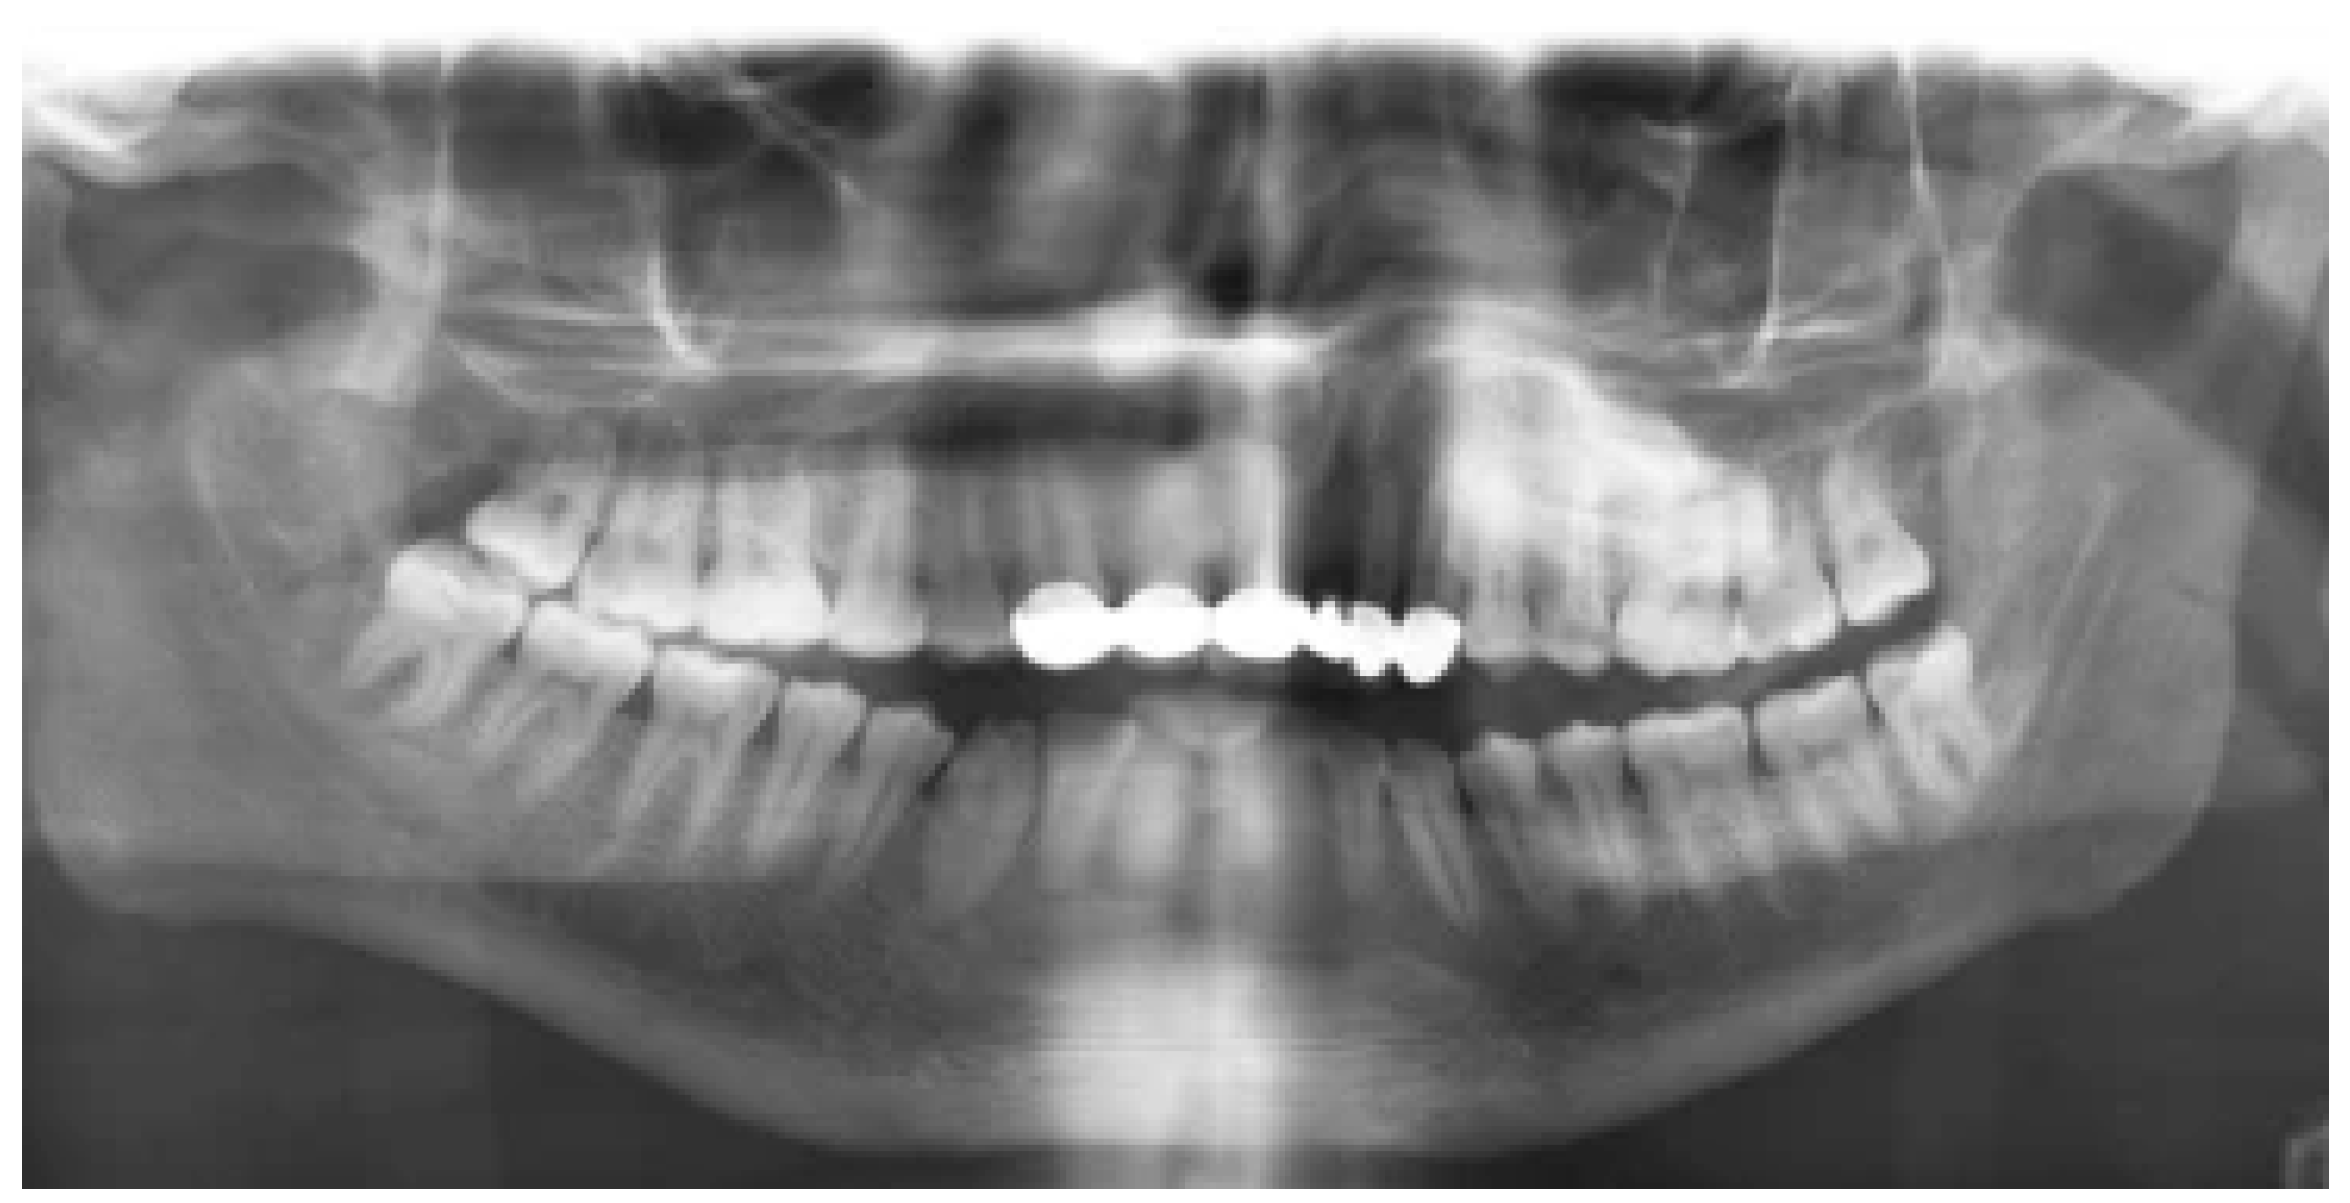

- Alali, Y.; Mohammed, W.; Aldrees, A.; Alshamrani, A.; Alabdullatif, M.; Alhajri, S. Comparative efficacy of digital panoramic radiograph and cone beam computed tomography in locating mandibular foramen. Eur. Rev. Med. Pharmacol. Sci. 2024, 28, 2996–3005. [Google Scholar] [PubMed]

- Yari, A.; Fasih, P.; Hosseini Hooshiar, M.; Goodarzi, A.; Fattahi, S.F. Detection and classification of mandibular fractures in panoramic radiography using artificial intelligence. Dentomaxillofacial Radiol. 2024, twae018. [Google Scholar] [CrossRef]

- Kaeppler, G.; Cornelius, C.-P.; Ehrenfeld, M.; Mast, G. Diagnostic efficacy of cone-beam computed tomography for mandibular fractures. Oral Surg. Oral Med. Oral Pathol. Oral Radiol. 2013, 116, 98–104. [Google Scholar] [CrossRef]